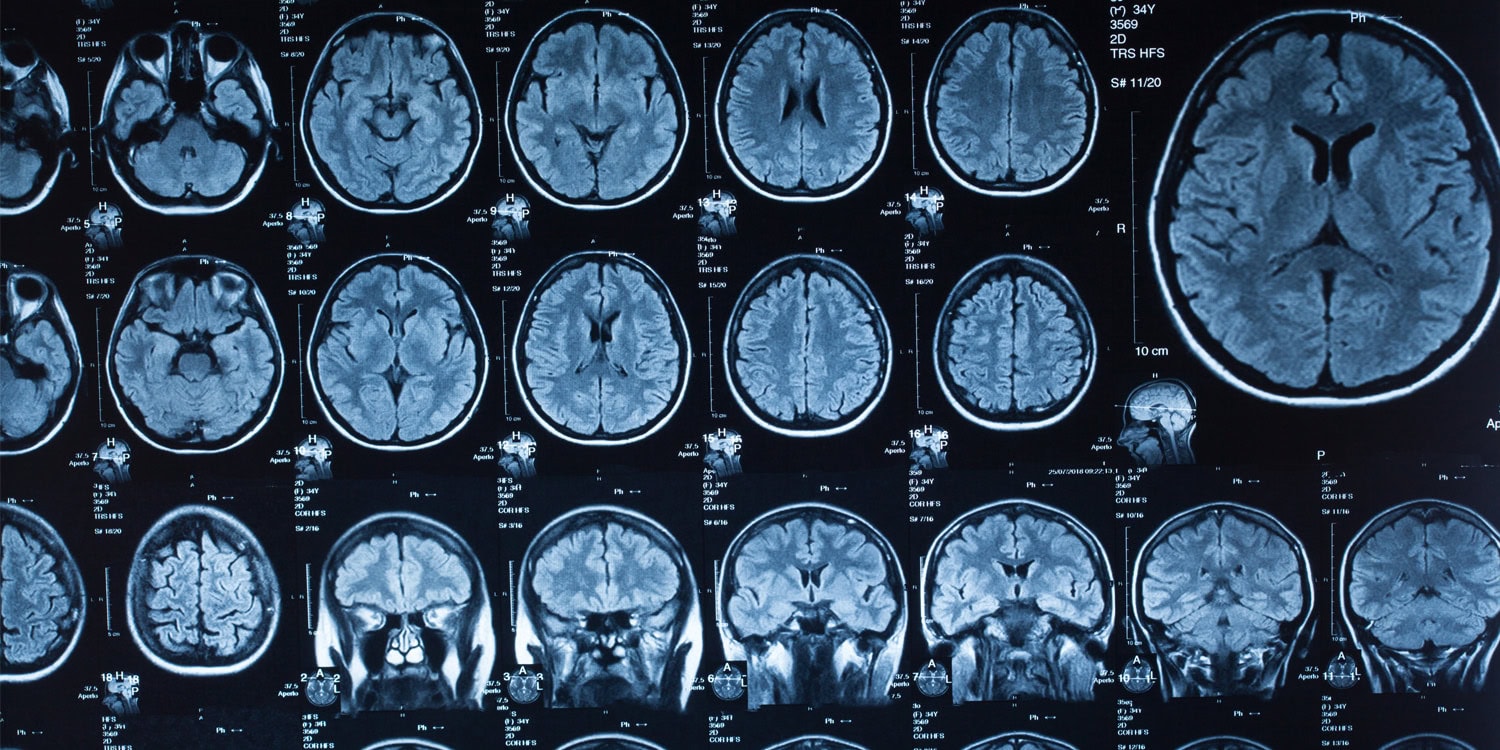

Анализируя тысячи МРТ-снимков людей — от младенцев, которым ещё и месяца нет, до любителей отмечать 90-летие, исследователи нащупали четыре ключевых перелома: примерно на 9, 32, 66 и 83 годах. Эти даты — не просто милые числа, а прямые маркеры капитального ремонта в нейроархитектуре. О таких результатах бодро отчитались в Nature Communications.